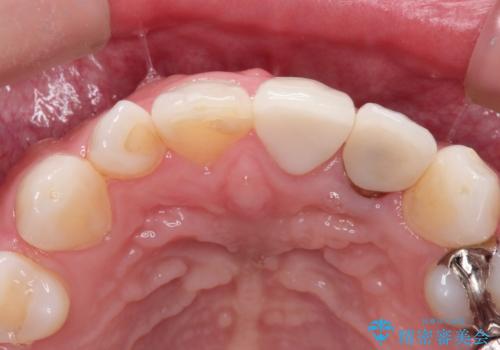

レントゲンを撮影すると、不適合のかぶせ物が装着されており、根管治療も不十分でした。

左上の1番目、2番目の歯を根管治療からの再治療を行う計画としました。

レントゲン上でも適合の良いかぶせ物が装着できています。